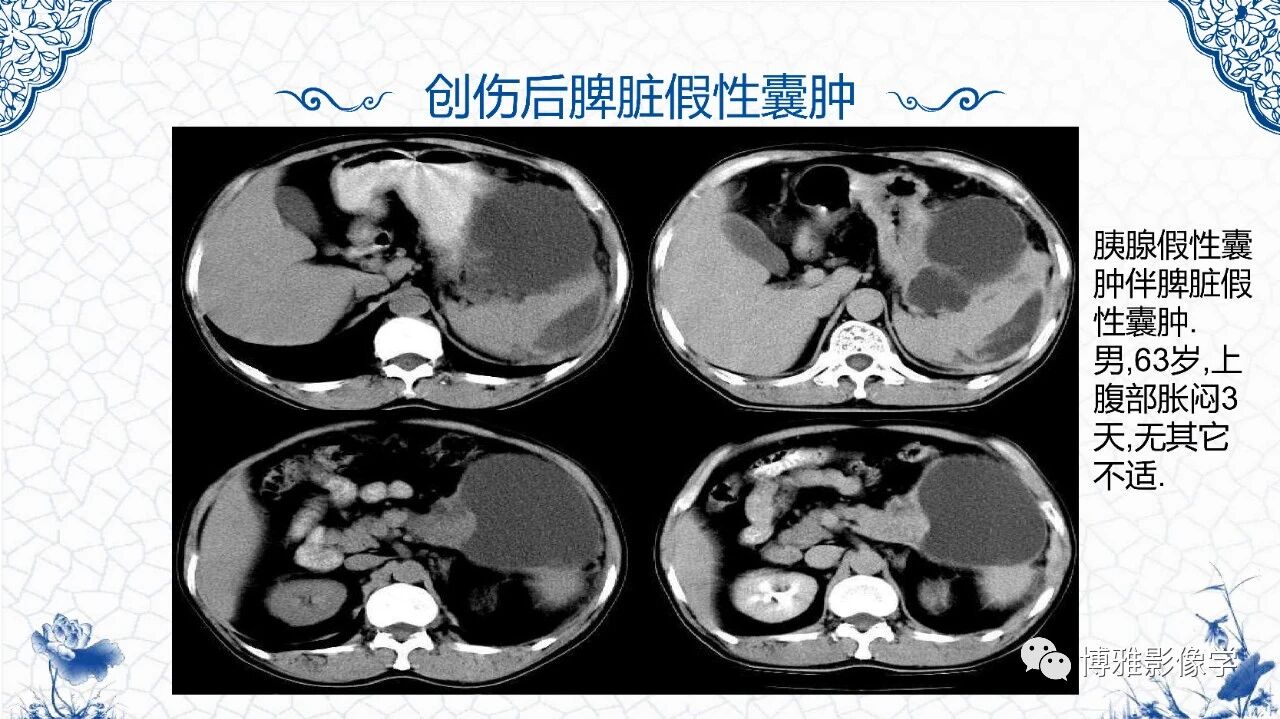

[腹盆] 脾脏非肿瘤影像诊断

脾脏非肿瘤影像诊断